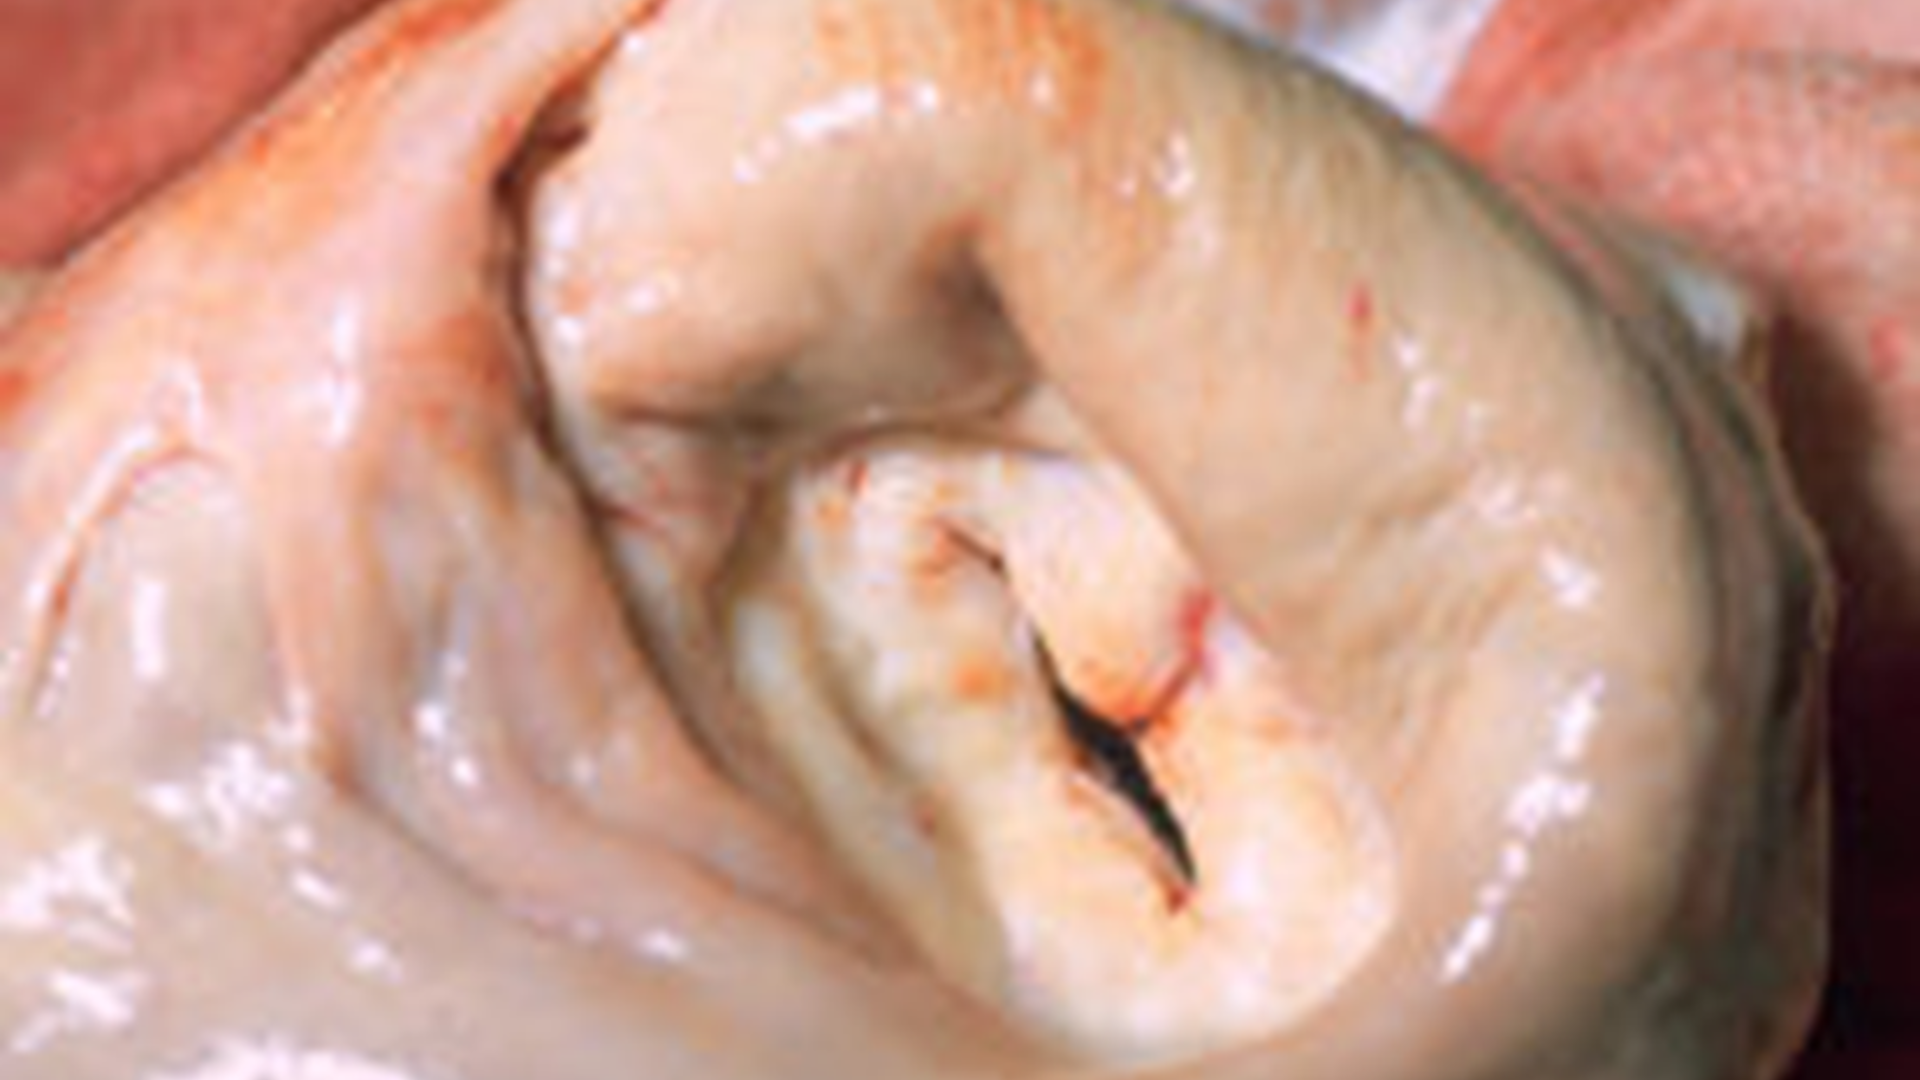

Mitral Valvular Diseases

• Mitral Stenosis

• Mitral Regurgitation